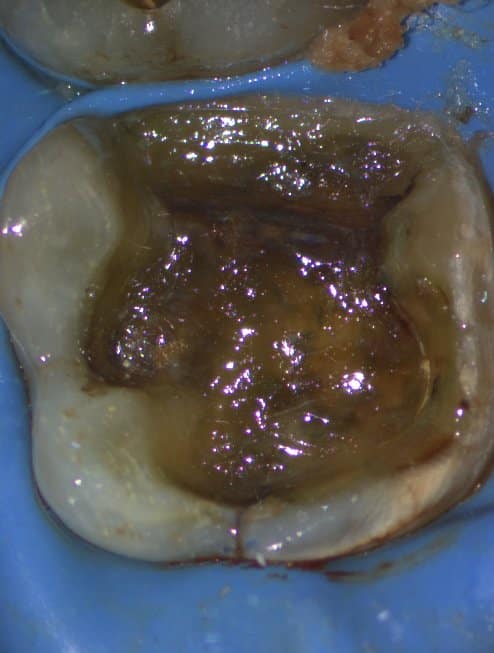

The patient complained of pain in the first mandibular molar during biting. This tooth showed an unacceptable amalgam restoration with caries underneath and a crack at the mesial side.

IDS

Resin Coat